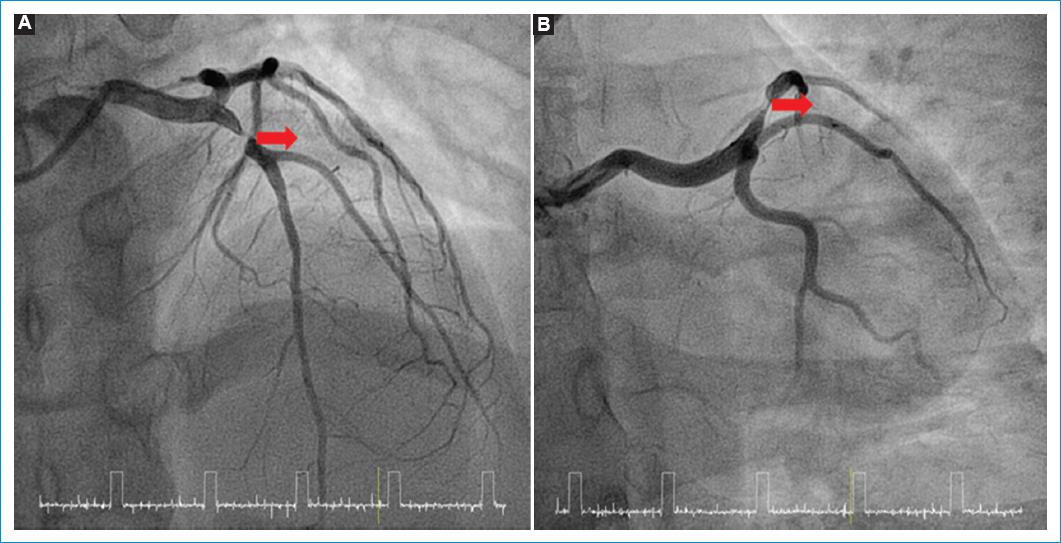

Se administró dosis de carga de 300 mg de ácido acetilsalicílico, 180 mg de ticagrelor vía oral y 60 mg de enoxaparina intravenosa. Con diagnóstico de infarto agudo de miocardio sin elevación del ST de alto riesgo (IAMSEST), se mantuvo monitorizada, sin que se registrara recurrencia del dolor y se trasladó la mañana siguiente a sala de hemodinámica para practicar una coronariografía. Esta mostró estenosis crítica de la arteria descendente anterior proximal (Figs. 1A y B). Se realizó angioplastia coronaria transluminal percutánea (ACTP) e implante de un stent de everolimus de 3.5/15 mm a 12 atm, con buen resultado angiográfico (Fig. 2). No se observaron lesiones en el resto de arterias coronarias. Su evolución posterior fue favorable. Se realizó ecocardiograma previo al alta, el cual mostró fracción de eyección ventricular izquierda del 68% sin asimetrías segmentarias.